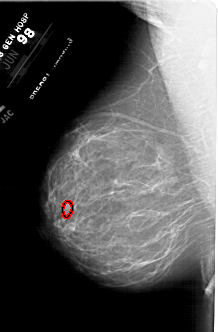

A_1787_1.LEFT_CC

LEFT_CC LINES 5641 PIXELS_PER_LINE 3796 BITS_PER_PIXEL 12 RESOLUTION 43.5 OVERLAY

FILE: A_1787_1.LEFT_CC.OVERLAY

TOTAL_ABNORMALITIES 1

ABNORMALITY 1

LESION_TYPE MASS SHAPE LOBULATED MARGINS ILL_DEFINED

ASSESSMENT 4

SUBTLETY 1

PATHOLOGY BENIGN

TOTAL_OUTLINES 1

BOUNDARY